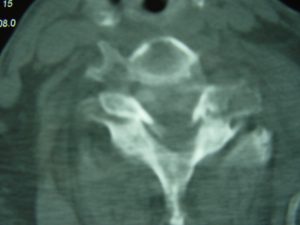

Εικόνα 4 (α,β) Προεγχειρητική Αξονική Τομογραφία Α.Μ.Σ.Σ. Εγκαρσία τομή (Axial) Παρατηρείται κάταγμα-εξάρθρημα του 6ου επί του 7ου αυχενικού σπονδύλου.